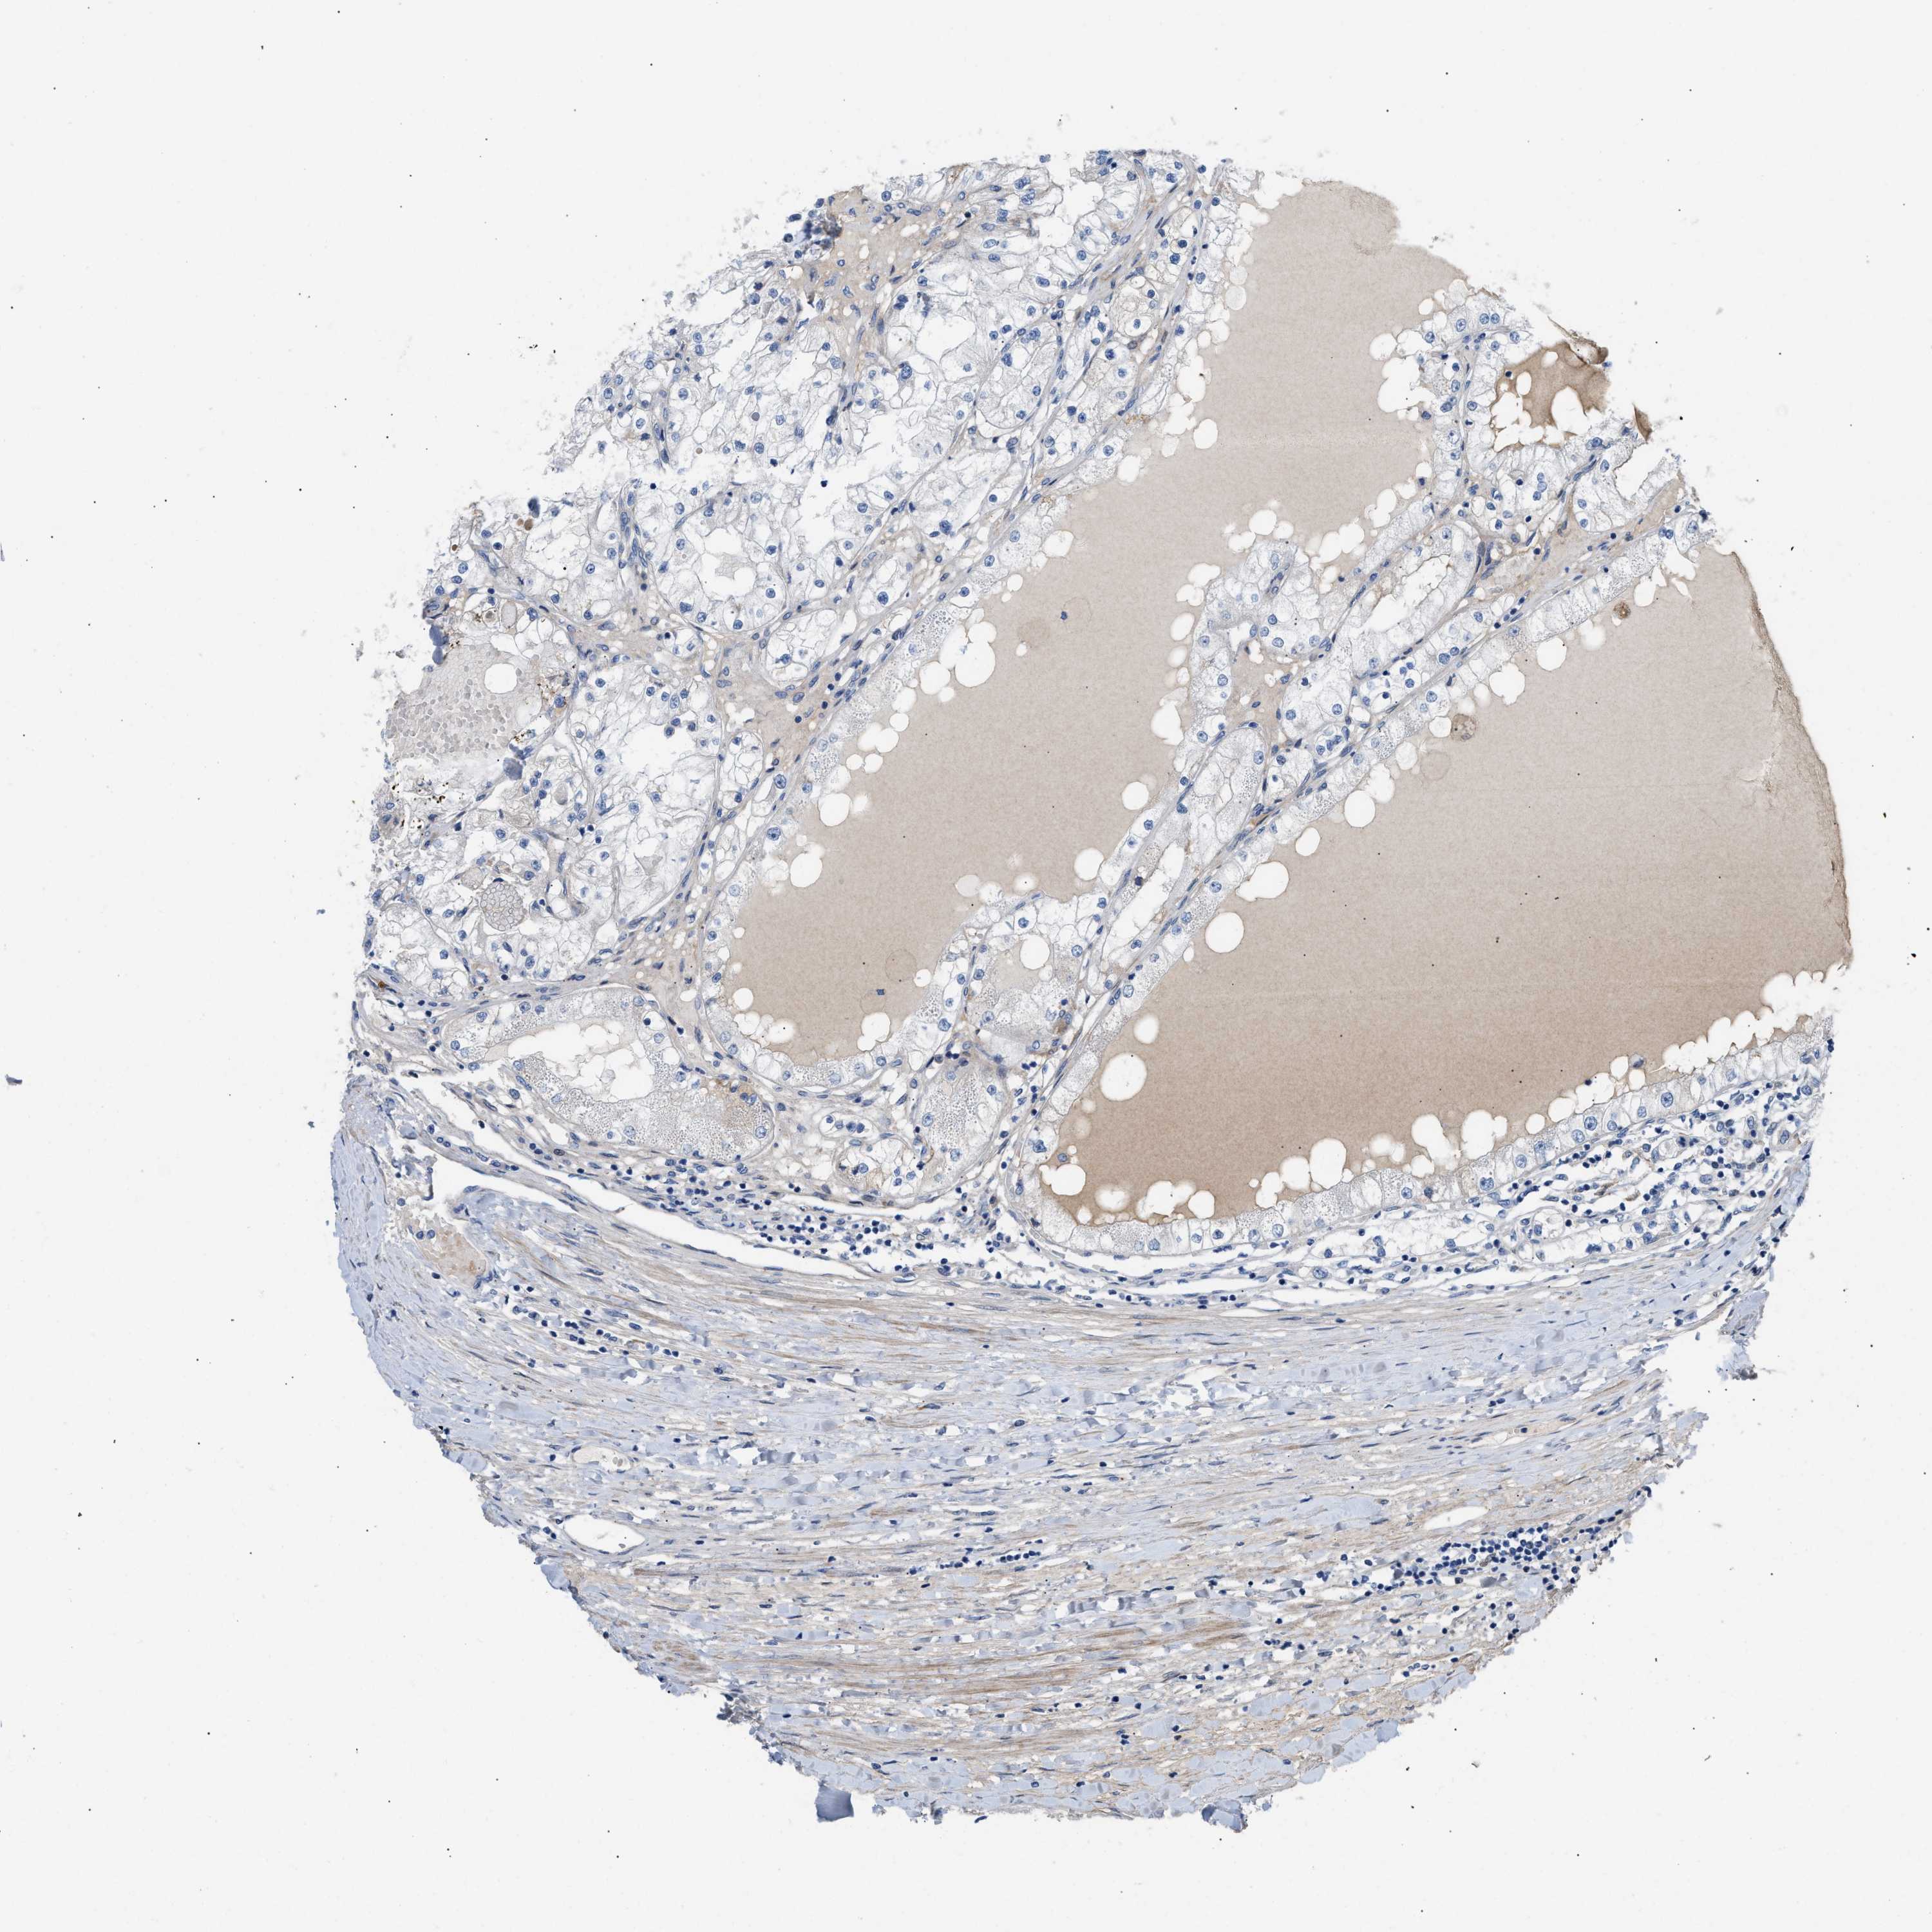

KIDNEY RENAL CLEAR CELL CARCINOMA (VALIDATION) - Interactive survival scatter ploti

The Survival Scatter plot shows the clinical status (i.e. dead or alive) for all individuals in the patient cohort, based on the same data that underlies the corresponding Kaplan-Meier plots. Patients that are alive at last time for follow-up are shown in blue and patients who have died during the study are shown in red.

The x-axis shows the expression levels (FPKM) of the investigated gene in the tumor tissue at the time of diagnosis. The y-axis shows the follow-up time after diagnosis (years). Both axes are complimented with kernel density curves demonstrating the data density over the axes. The top density plot shows the expression levels (FPKM) distribution among dead (red) and alive patients (blue). The right density plot shows the data density of the survived years of dead patients with high and low expression levels respectively, stratified using the cutoff indicated by the vertical dashed line through the Survival Scatter plot. This cutoff is automatically defined based on the FPKM cutoff that minimizes the p-score. The cutoff can be changed by dragging the vertical line or by entering a cutoff value in the square labeled "Current cut-off".

Under the Survival Scatter plot the p-score landscape (black curve; left axis) is shown together with dead median separation (red curve; right axis). Dead median separation is the difference in median mRNA expression between patients who have died with high and low expression, respectively. It is calculated as follows: median FPKM expression of dead patients with high expression - median FPKM expression of dead patients with low expression. This is intended to aid the user in visually exploring custom cutoffs and the associated p-scores and dead median separation.

Individual patient data is displayed and can be filtered by clicking on one or more of the category buttons on the top of the page. Categories describing expression level and patient information include: high, low, alive, dead, female, male and tumor stages. The scale of the x-axis can be toggled between linear and log-scale by clicking on the "x log" button. Mouse-over function shows TCGA ID, patient information and mRNA expression (FPKM) for each patient.

& Survival analysisi

Kaplan-Meier plots summarize results from analysis of correlation between mRNA expression level and patient survival. Patients were divided based on level of expression into one of the two groups "low" (under cut off) or "high" (over cut off). X-axis shows time for survival (years) and y-axis shows the probability of survival, where 1.0 corresponds to 100 percent.

TFPI is not prognostic in Kidney Renal Clear Cell Carcinoma (validation)

: 192.37

Average pTPM 127.8

Number of samples 100